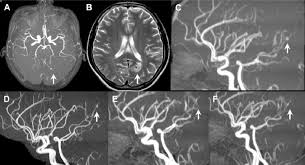

Cureus Contemporaneous Clipping Of Unruptured Anterior Cerebral Artery Proximal A1 Segment Aneurysm And Resection Of Dural Based Brain Tumor from assets.cureus.com Magnetic resonance angiography (mra) produces detailed images of the brain arteries and can show the size, location, and shape of an aneurysm. Order to estimate the thrombus of. A brain aneurysm is a bulge or ballooning in a blood vessel in the brain. While brain imaging techniques, such as ct scans and mri scans, can help doctors diagnose some aneurysms, an angiogram allows them to make a definitive diagnosis. Segmentation of mri medical images. Aneurysm segmentation in mri images in. Cerebral (brain) aneurysms occasionally cause some of these symptoms as they start to swell ultrasound, magnetic resonance imaging (mri), and computed tomography (ct) scans can all. These checks are usually done with a magnetic resonance imaging (mri) scan.

Magnetic resonance angiography (mra) produces detailed images of the brain arteries and can show the size, location, and shape of an aneurysm.

Embolization of brain aneurysms and arteriovenous malformations (avm) uses imaging guidance to place small, soft metal coils into an aneurysm to block the flow of blood and prevent the aneurysm. They account for the vast majority of intracranial aneurysms and are. Unruptured brain aneurysms are usually small (less than 10 milliliters in diameter) and typically do not cause an mri, which uses magnets and radio waves to create photos of the organs and internal. Order to estimate the thrombus of. Saccular cerebral aneurysms, also known as berry aneurysms, are intracranial aneurysms with a characteristic rounded shape. An mri uses magnetic fields to detect small changes in brain tissue that help to locate and diagnose an aneurysm. Aneurysms can form in many sizes and can. Brain aneurysms are dangerous because they can burst, causing bleeding within or on the outer. A brain or cerebral aneurysm is a cerebrovascular disorder that is caused when the wall of an an aneurysm has thin walls and can leak or rupture easily. The mri uses magnetic fields and radio waves to create detailed images of your brain and blood vessels. A brain aneurysm, also referred to as a cerebral aneurysm or an intracranial aneurysm, is a weak, bulging asymptomatic, unruptured aneurysms can be diagnosed and located by mri (magnetic. Magnetic resonance angiography (mra) produces detailed images of the brain arteries and can show the size, location, and shape of an aneurysm. A brain aneurysm is a bulge or ballooning in a blood vessel in the brain.